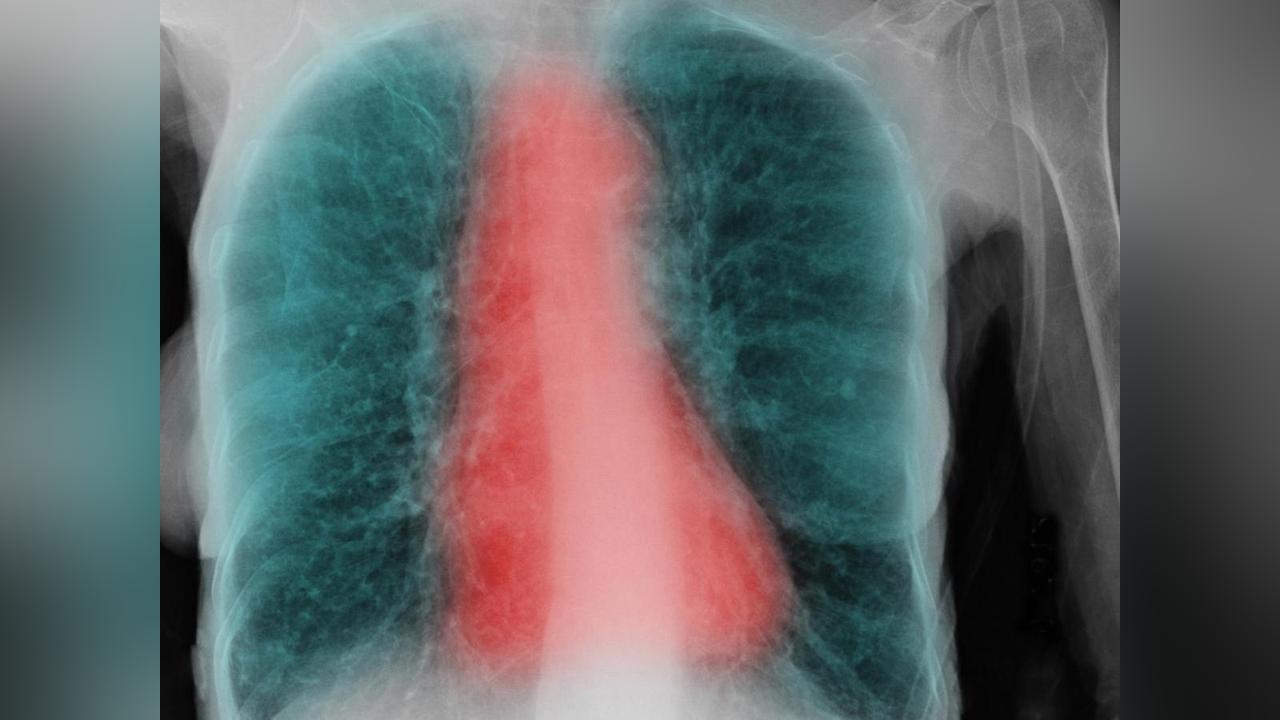

Selon une nouvelle étude américaine, la réponse se situerait au niveau de l’anatomie des malades. L’équipe a examiné les résultats d’imagerie de plus de 6.500 adultes fumeurs ou non, atteints de BPCO ou non, observés dans trois études (MESA, SPIROMICS et CanCOLD). Elle se rend alors compte qu’une anomalie est significativement plus présente chez les malades: la dysanapsie. En clair, ces patients ont des voies aériennes (les bronches) étroites au regard de la taille de leurs poumons. Ayant une capacité respiratoire plus restreinte que la normale, ces personnes sont plus susceptibles de souffrir de BPCO. « Ces résultats montrent que des voies aériennes plus petites par rapport à la taille des poumons sont un facteur de risque très important pour la BPCO », explique dans un communiqué le Dr Benjamin Smith, auteur principal de l’étude. Ces résultats confirment une étude précédente observant la fonction pulmonaire de malades sur trois décennies. Elle avait démontré que 50 % des BPCO chez les personnes âgées sont dues à une fonction pulmonaire de base faible, plutôt qu’à son déclin accéléré.

Ces scans des voies aériennes (en rouge) et des poumons (en noir) montrent le spectre de la dysanapsie, avec des voies aériennes plus petites en proportion de la taille des poumons (gauche) par rapport aux voies aériennes de taille normale (milieu), et plus grandes que les voies aériennes normales (droite). Cliquez pour voir en plus grand. Crédit: VIDA Apollo Software, courtesy of Eric A. Hoffman, PhD, Radiology, University of Iowa Carver College of Medicine.